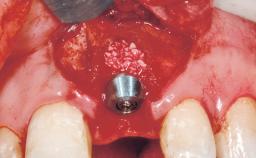

Immediate Flapless Placement of an Implant in a Maxillary Right Lateral Incisor Site

This 43-year-old male patient, a non-smoker, came to our practice because of a fracture of tooth 12 caused by a bicycle accident. Due to the combined para- and infrabony crown and root fracture, tooth extraction, and subsequent implant placement were suggested to the patient as the therapy of choice. The patient had high esthetic expectations with regard to the treatment outcome and asked for an immediate fixed provisional restoration. His individual esthetic risk profile summed up to a medium esthetic risk.

Placement Protocol Immediate implant placement

Tooth Site Maxillary incisor or canine

Socket Morphology Single-root socket

Socket Integrity Sufficient, with intact bone walls

Bone Volume Sufficient, with intact walls